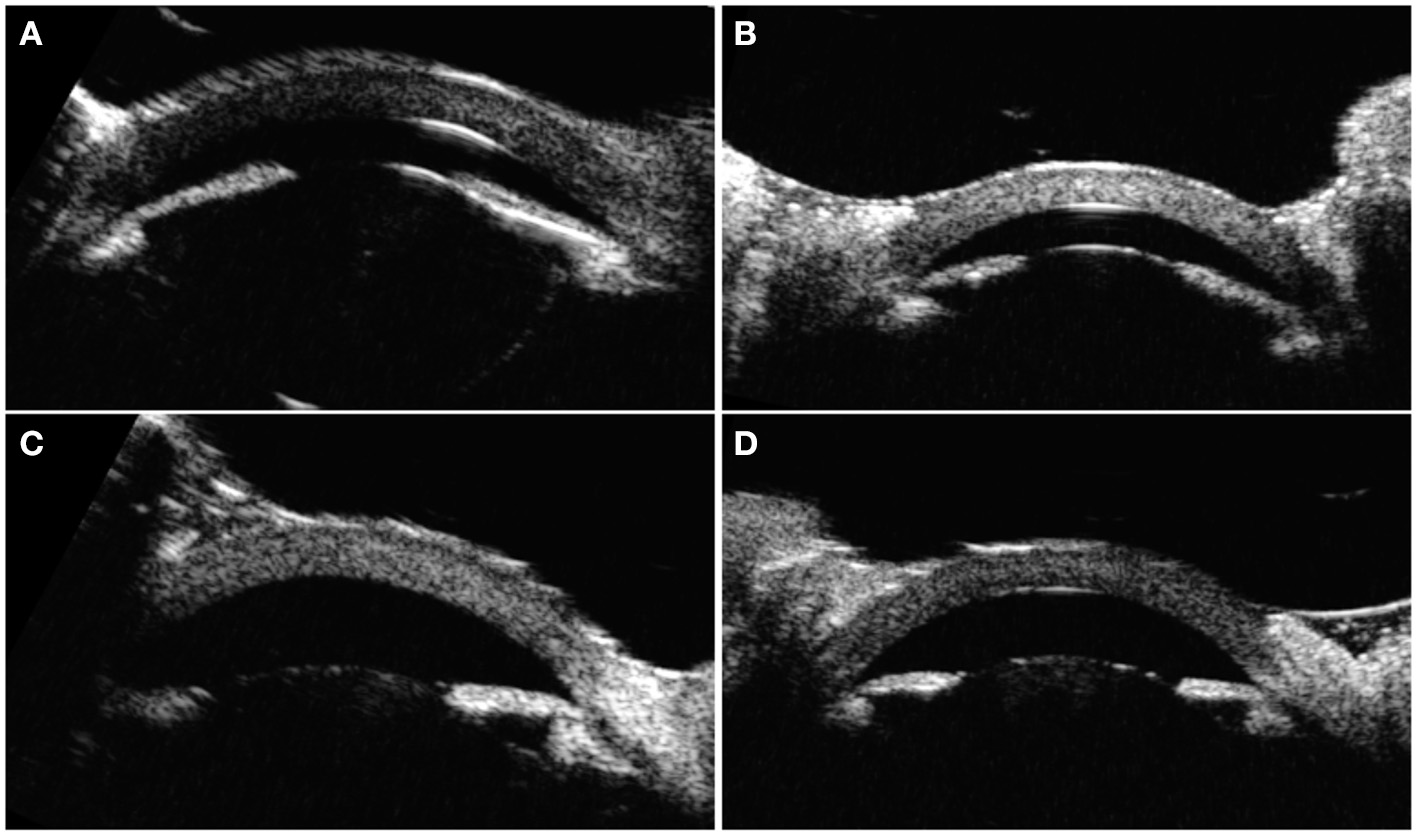

On exam and diagnostic imaging with B-scan ultrasound, there was no rubeosis, and no choroidal or retinal detachments were noted (Figure 2). Clinical examination and ultrasound biomicroscopy (UBM) revealed significant anterior chamber shallowing without pupillary block or synechiae, which improved significantly with topical cycloplegia with cyclopentolate 0.5% (Figure 3). With oral acetazolamide and topical IOP-lowering eyedrops, her pressures improved but were still elevated to the 30- to 35-mmHg range, and the corneal clouding still prevented adequate gonioscopic visualization of angle anatomy. Fundus examination revealed persistent stage 3 ROP with inadequate laser, particularly nasally; however, the view was still somewhat limited for additional laser photocoagulation (Figure 1). She underwent intravitreal injection of bevacizumab 0.625 mg in both eyes at 39 weeks of PMA. In both eyes, regression of ROP after laser and intravitreal bevacizumab was noted by 41 weeks of PMA (2 weeks after injections). Despite moderate improvement in the anterior chamber depth (Figure 3) and IOP, medical treatments were ultimately determined to be inadequate, and the patient required ab externo trabeculotomy in the right eye at 42 weeks of PMA and left eye at 44 weeks of PMA. With parental consent, genetic screening for congenital glaucoma through the Prevention Genetics Glaucoma Panel was obtained and found to be negative.

Figure 3. Ultrasound biomicroscopy images taken at 40 and 41 weeks of PMA. (A) Right eye before cyclopegia. (B) Left eye before cyclopegia. (C) Right eye after cyclopegia. (D) Left eye after cyclopegia.